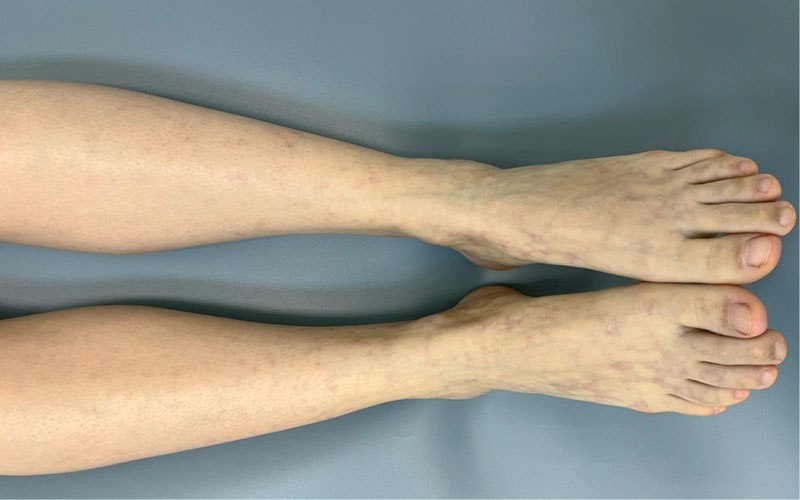

Рис. 8. Пациентка с ЛВ без язв до проведения комплексной терапии с применением НТАП

В обеих группах после проведенного лечения наблюдалась положительная динамика в виде исчезновения онемения и боли в нижних конечностях, активации заживления язвенных дефектов, уменьшения выраженности ливедо, но при присоединении к основной терапии процедур низкотемпературной аргоновой плазмы наблюдалось более выраженное улучшение со стороны кожного процесса у пациентов группы исследования по сравнению с группой контроля (рис. 4–14).